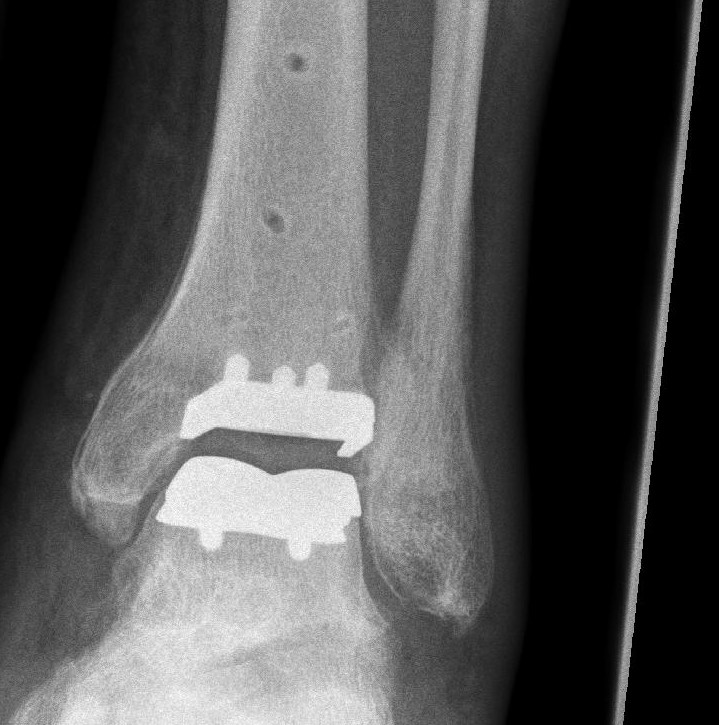

Das Kunstgelenk

Bei hochgradigem Verschleiß ist eine Wiederherstellung des Gelenkknorpels nicht mehr möglich. In diesen Fällen ist das Einbringen eines Kunstgelenkes oder die Versteifung das Mittel der Wahl. Nach Implantation einer Totalendoprothese des oberen Sprunggelenkes bleibt die Beweglichkeit des Fußes erhalten. Das Gangbild verändert sich nach diesem Eingriff nicht.

Allerdings eignet sich nicht jeder Patient zur Implantation eines Kunstgelenkes. Insbesondere bei jungen, aktiven Patienten kommt es häufig zu frühzeitigen Lockerungen des Implantates. Außerdem ist bei Arthrose des oberen und des unteren Sprunggelenkes oder extremen Fußfehlstellungen das Einbringen eines Kunstgelenkes nicht sinnvoll.

Das Kunstgelenk besteht aus drei Teilen. Zwei titanbeschichtete Metallelemente haben spezielle Zapfen und können mittels Verklemmungstechnik stabil im Knochen verankert werden. Ein drittes Element aus Kunststoff wird als Zwischenscheibe eingebracht.

Bereits nach zwei Wochen kann die Physiotherapie beginnen und der Fuß in einem Aircastwalker voll belastet werden.